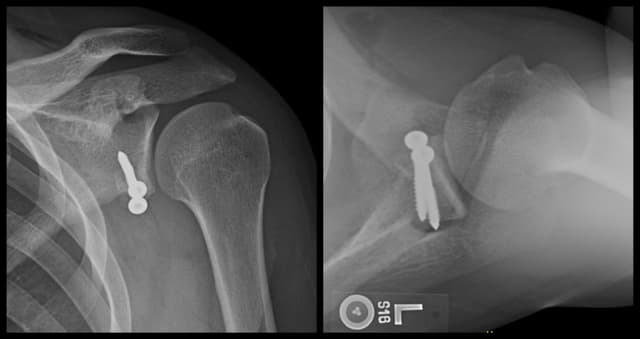

Latarjet Procedure